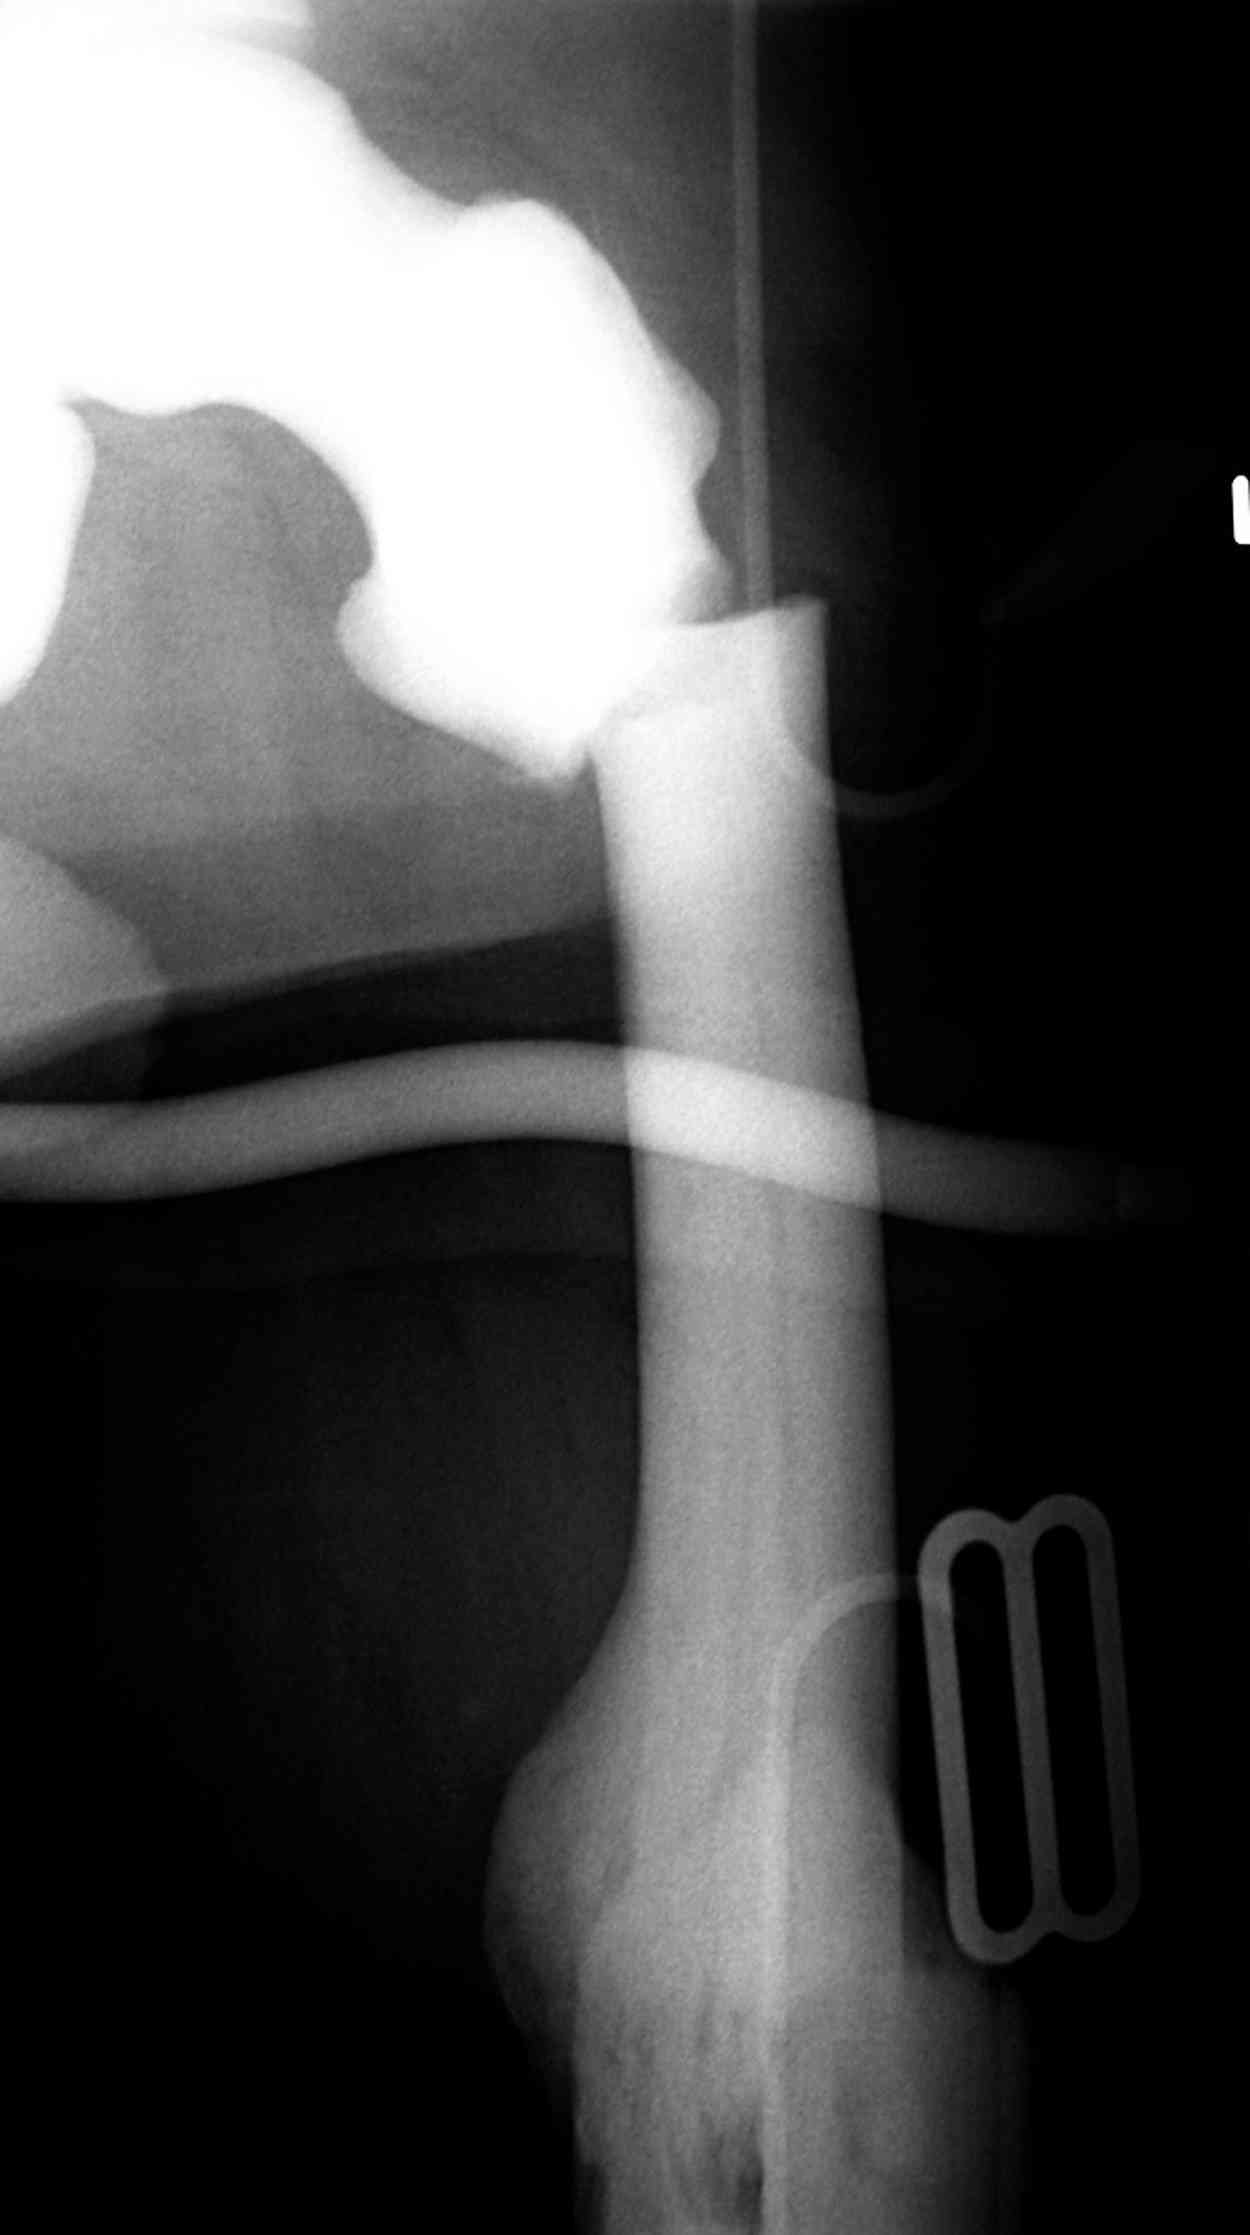

Здесь у меня дополнительные снимки с большим разрешением и в разных режимах, а то те дигитал снимки совсем очень блеклые, может, эти изображени изменят выбор тактики

После неудачной попытки скелетного вытяжения в первом мед.учреждении, после осмотра снимков и изучения истории, поставили диагноз “Остеопетроз” или мраморная болезнь, редкая наследственная костная паталогия, где имеется нарушение формации остеокластов.

Не вызывает ли подозрение, что отсутствует медуллярный канал, как просверлить канал?

Канал, возможно, действительно запаян. Но разве большие проблемы его создать и рассверлить (если только это мраморная болезн?) Уверен, в вашей клинике есть для этого всё.

Djoldas Kuldjanov >как просверлить канал?

1. Верхушку б\вертела всктыть спицей и рассверлить каннюлированным инструментом (14 мм).

2. Если в диафизарной части канал запаян, то, используя сам штифт, введенный в проксимальный отломок, как центратор, по нему завести спицу в центр дистального отломка и сформировать канал, сначала тонкий 4 мм.

3. Гибкими (неканнюлированными) развертками диаметром 6,7 и 8 мм последовательно расширить канал.

4. Рассверливать каннюлироваными развертками по направляющей спице до нужного диаметра.